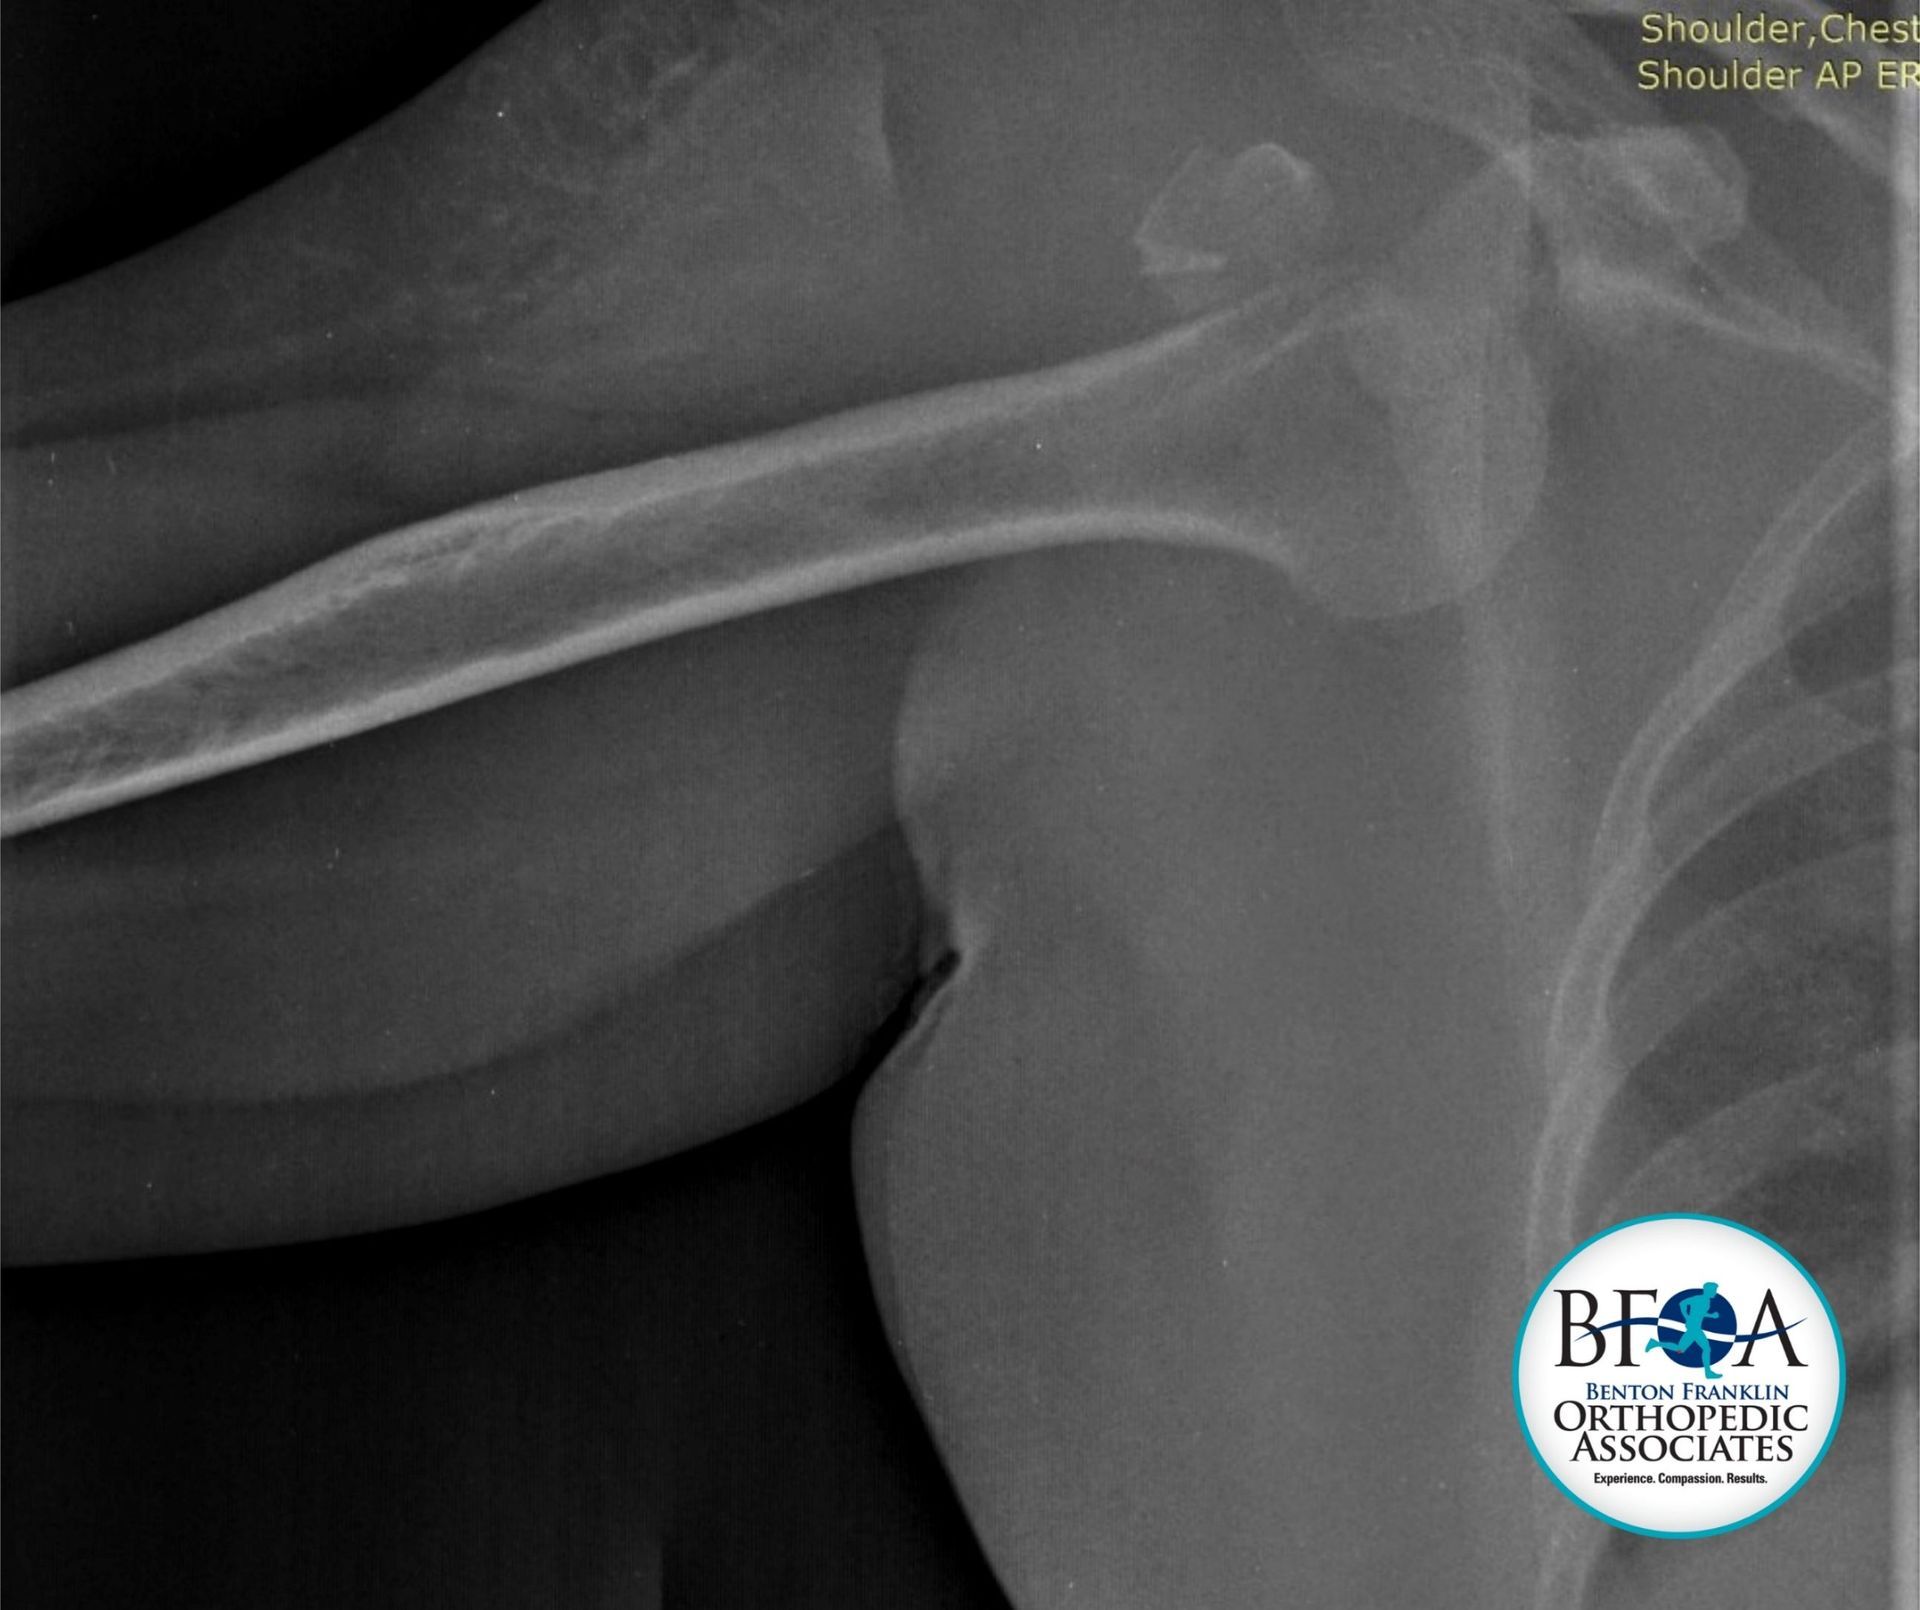

Shoulder Dislocations

A shoulder dislocation happens when the head of the humerus (upper arm bone) pops out of the shoulder socket, often due to trauma or forceful overhead movements. Risk factors include athletic injuries, falls, or accidents. Shoulder joints are particularly vulnerable because of their wide range of motion.

- Drew-on exams, X-rays, and sometimes MRI for precise injury assessment